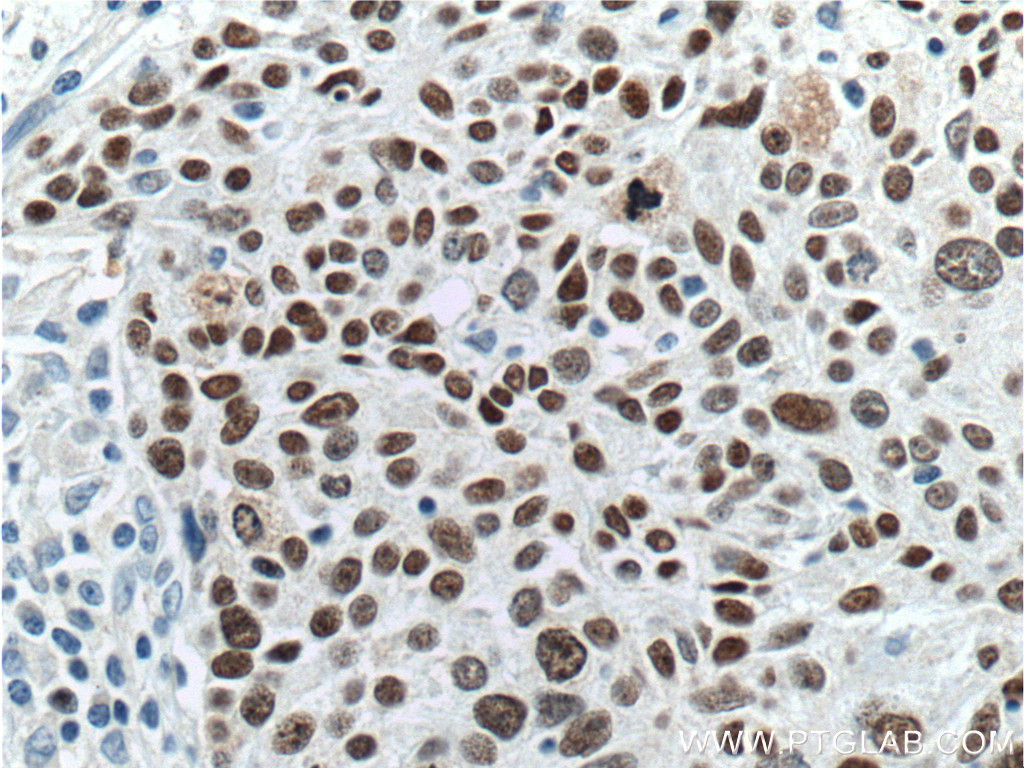

Sox2 est une protéine de 317 acides aminés. Son poids moléculaire est de 34 310 Da. Son hydrophobicité est de -0,7. La protéine Sox2 possède une région nommée boîte-HMG de 69 acides aminés. C’est une protéine exprimée dans le noyau cellulaire.